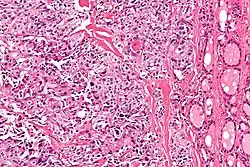

يتم إجراء التشخيص في المقام الأول عن طريق الخزعة بالإبرة الدقيقة لآفة الغدة الدرقية لتمييزها عن أنواع أخرى من آفات الغدة الدرقية.[9] سيظهر الفحص المجهري سدى نشواني مع تضخم في الخلايا المجاورة للجريب.